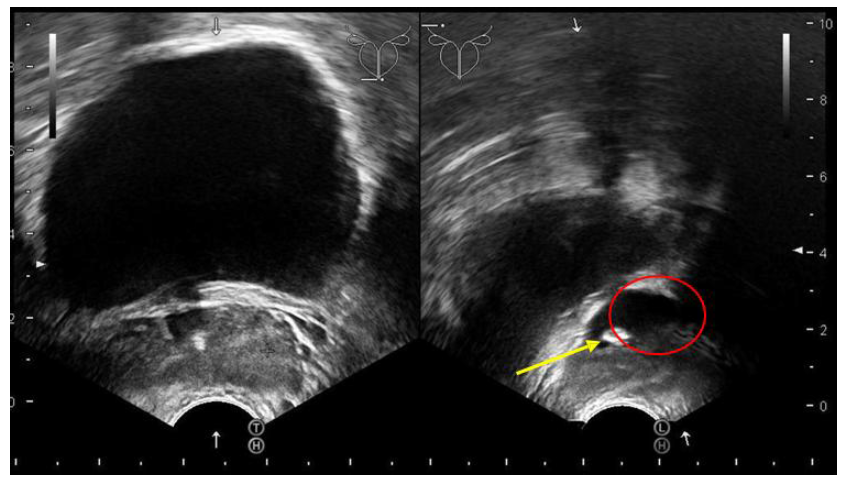

We wanted to get to the bottom of the patient's symptoms, so we started off by doing a transrectal ultrasound exam. The scan revealed that the left seminal vesicle was noticeably swollen and had a bright lesion inside it—which, along with a trailing shadow, pointed pretty clearly to a stone (Figure 1).

Figure 1: A transrectal sonography revealed that a 7 mm Stone (yellow arrow) with seminal vesicle (red circle) enlargement.